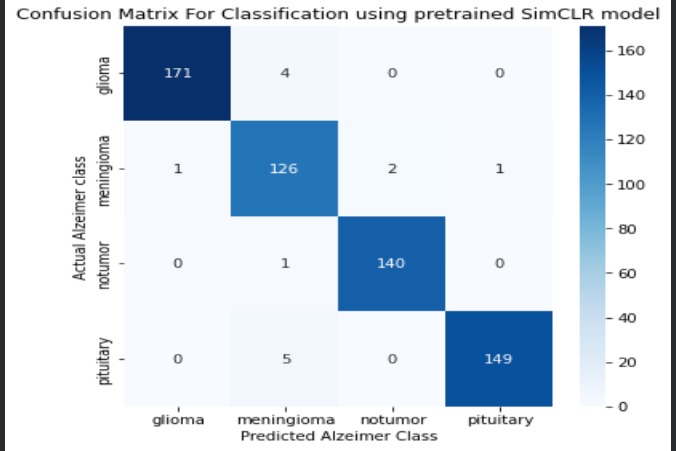

Confusion Matrix for Tumor